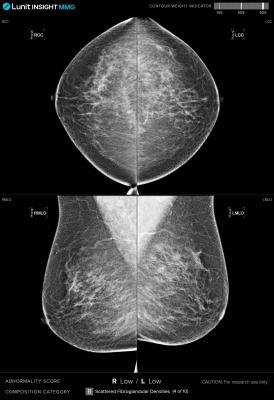

July 29, 2024 — Lunit, a leading provider of AI-powered solutions for cancer diagnostics and therapeutics, announced the implementation of its AI-powered breast cancer detection solution, Lunit INSIGHT MMG, in Qatar's national breast cancer screening program. This marks the first nationwide adoption of AI in a national-level breast screening workflow in the Middle East. The partnership, set for an initial period of five years, demonstrates a long-term commitment to advancing breast cancer screening in Qatar.

Starting June 2024, Qatar's Primary Health Care Corporation (PHCC) has integrated Lunit INSIGHT MMG into its "Screen for Life" program, the country's national breast and bowel cancer screening initiative. The AI solution aims to enhance early detection of breast cancer, potentially reducing missed diagnoses and improving survival rates in Qatar's triennial screening program.

The implementation follows a successful retrospective validation phase that began in March 2023. Satisfied with the performance and added value, two radiologists now read each mammogram while referring to Lunit INSIGHT MMG's results, improving accuracy and efficiency in the screening process.